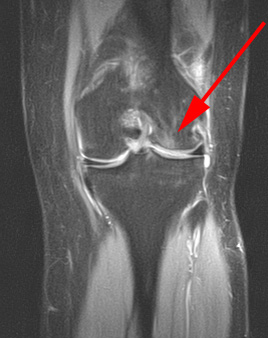

Knæ, Bone-Bruise, MR 1

MR-skanning af knæet der viser småfrakturer i trabeklerne (bone bruise) hos to forskellige patienter. Denne slags småfrakturer er ikke synlige på en almindelig røntgenoptagelse.